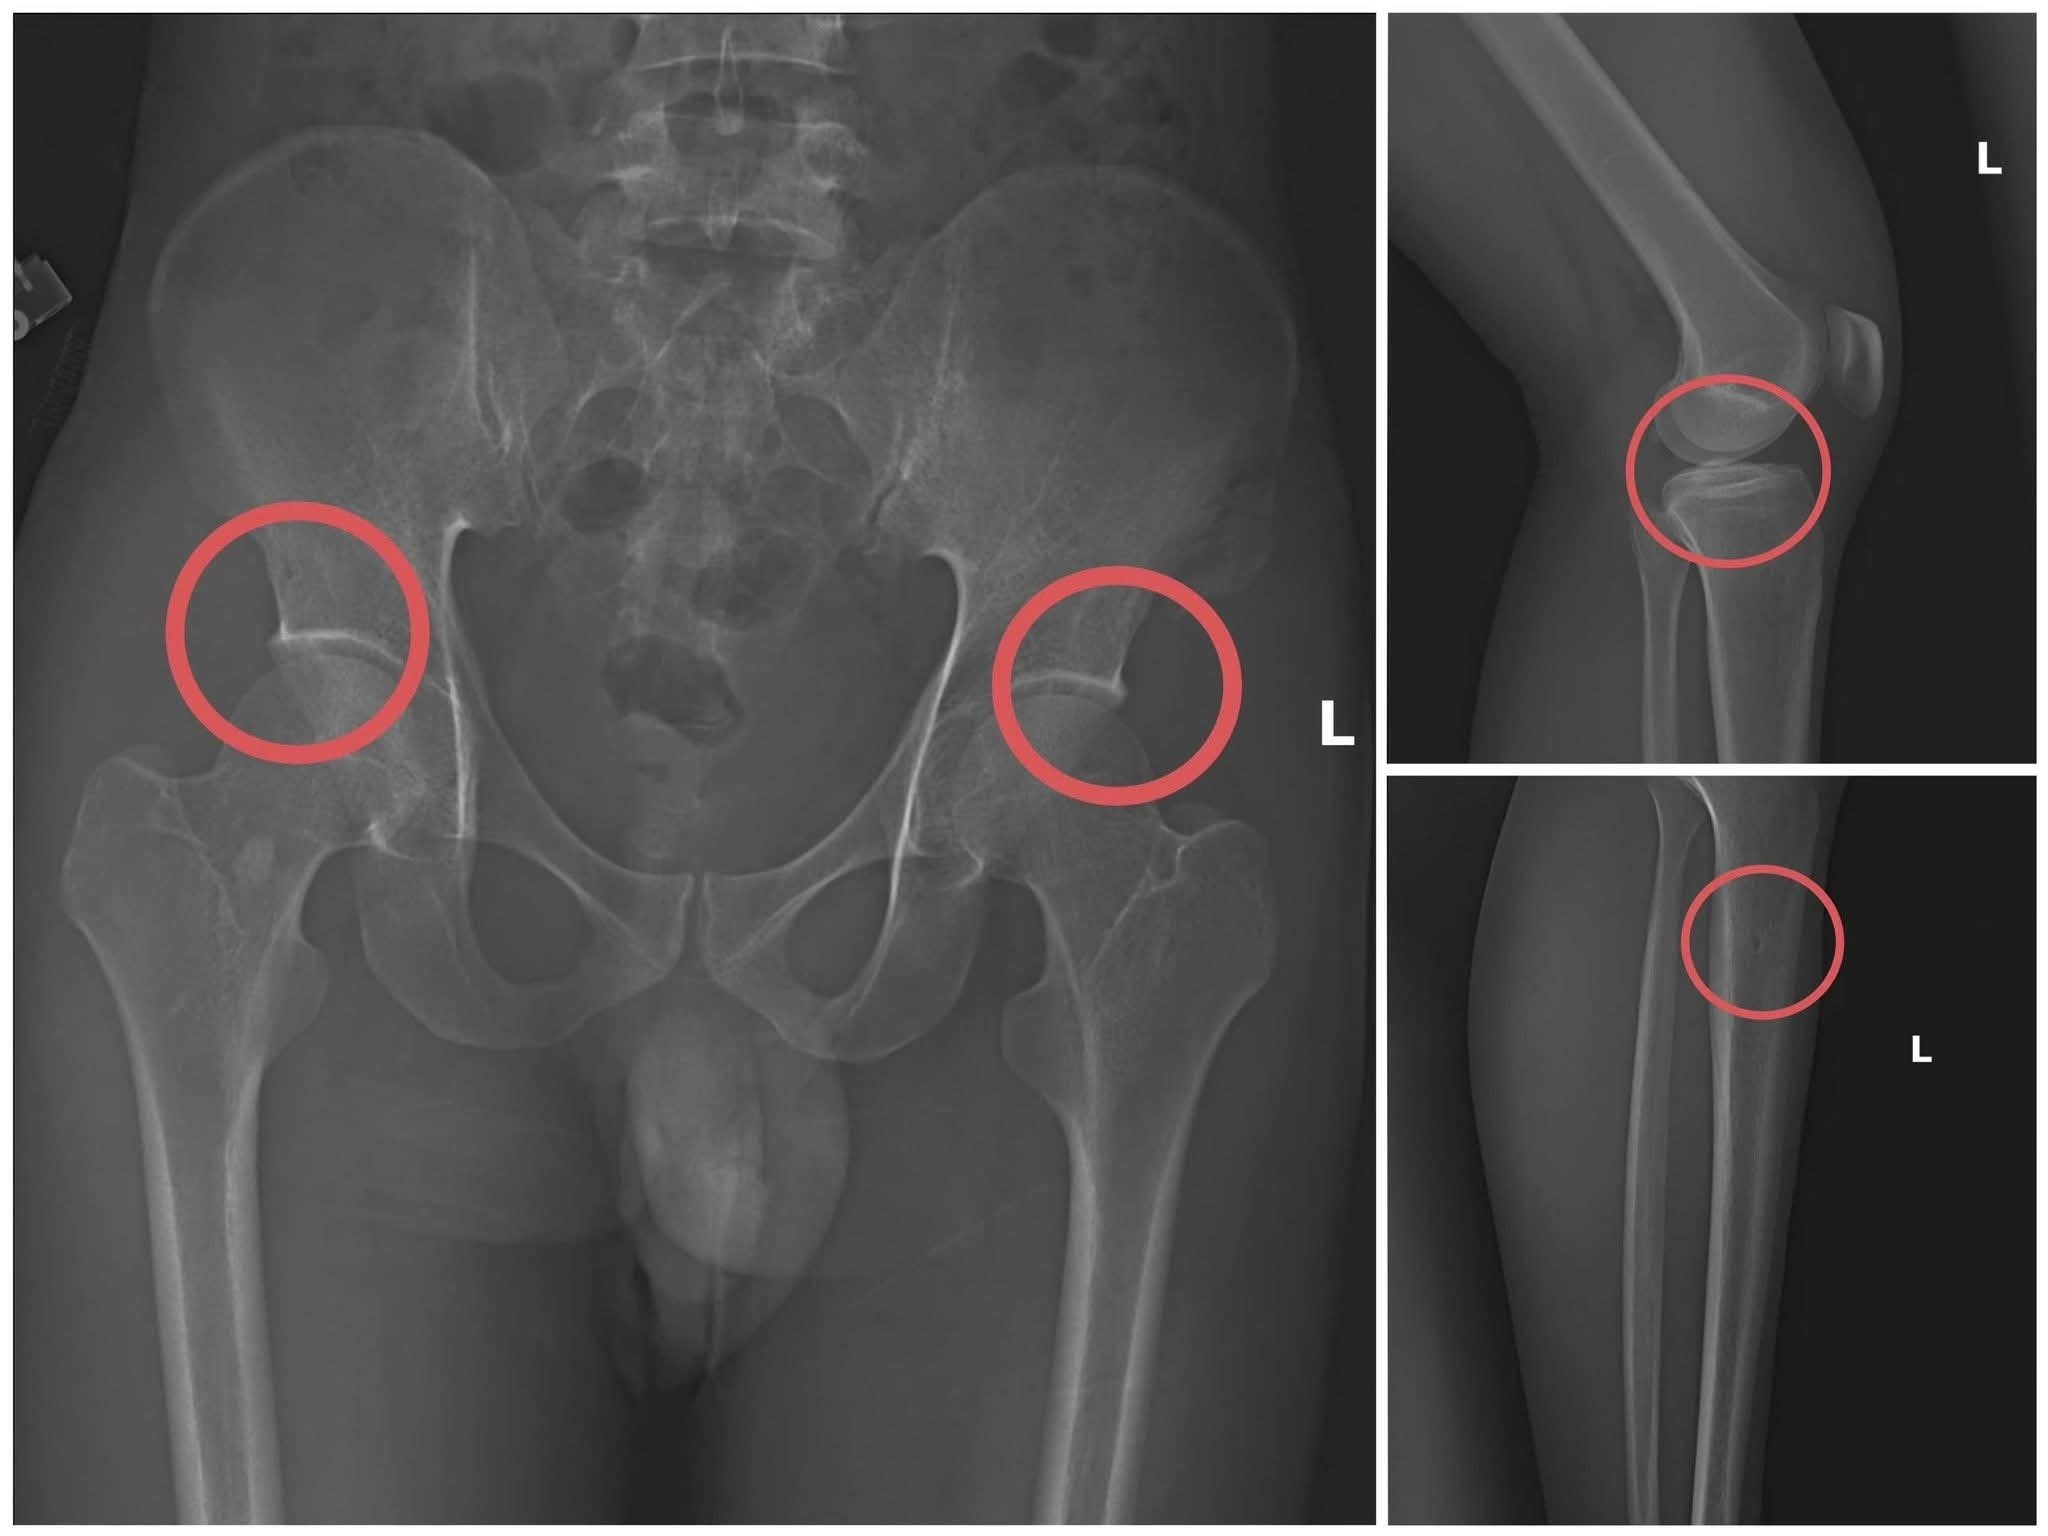

Lợi dụng kinh nghiệm công tác lâu năm trong ngành y và am hiểu sâu sắc về cấu tạo xương khớp cũng như cơ chế chi trả bảo hiểm cho các thương tích gãy xương giá trị cao, Châu đã thiết lập một quy trình trục lợi tinh vi, từ việc vận động người tham gia mua bảo hiểm, tổ chức gây thương tích, đến hợp thức hóa hồ sơ bệnh án.

Điều khiến dư luận rúng động là Tạ Minh Châu đã trực tiếp thực hiện hành vi tiêm thuốc mê, sau đó sử dụng kim tiêm, búa và các công cụ khác để tác động lên xương người mua bảo hiểm, tạo ra các vết nứt, vỡ xương khớp tương tự như một tai nạn thật sự.

Thiếu tướng Nguyễn Minh Tuấn, Giám đốc Công an tỉnh, nhận định thủ đoạn này không chỉ tàn nhẫn, vô nhân tính và coi thường tính mạng người tham gia, mà còn được tính toán kỹ lưỡng nhằm gây thương tích đúng vị trí có mức chi trả cao, khiến các công ty bảo hiểm khó lòng phát hiện dấu hiệu gian dối.

Khi đã tạo xong thương tích, Châu tiếp tục hướng dẫn đồng phạm dựng hiện trường giả như trượt chân ngã suối, điện giật ngã... để hợp thức hóa bệnh án và hoàn thiện hồ sơ yêu cầu chi trả.